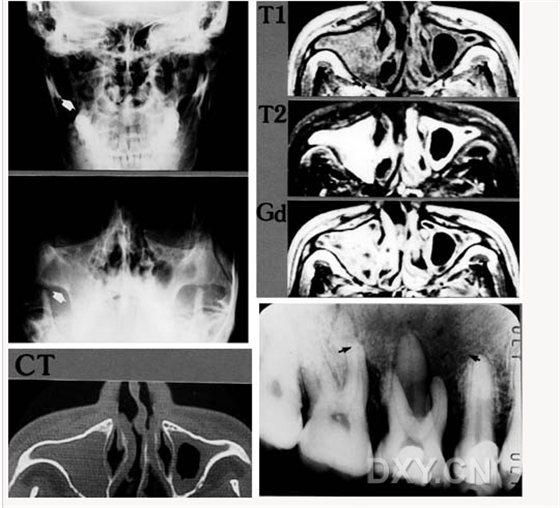

鼻竇炎(注意不要誤診呀)

良性成牙骨質細胞瘤